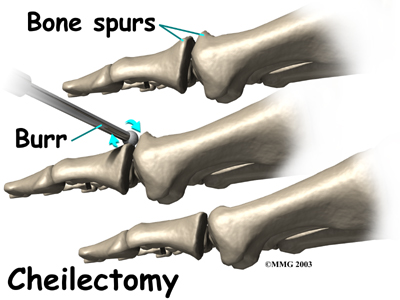

In some cases bone spurs that form on the top of the joint can bump together when the big toe bends upward, or extends. This causes a problem when walking because the big toe needs to bend upward when the foot is behind the body, in order to take the next step. The constant irritation when the bone spurs bump together leads to pain and difficulty walking.

A cheilectomy is a procedure to remove the bone spurs at the top of the joint so that they don't bump together when the toe extends. This allows the toe to bend better and reduces the amount of pain while walking. To perform a cheilectomy, an incision is made along the top of the joint. The bone spurs that are blocking the joint from extending are identified and removed from both the bones that make up the joint. A little extra bone may be taken off to ensure that nothing rubs when the hallux is raised. The skin is closed and allowed to heal.

There are other surgical procedures that are slight variations of these three approaches. For example, cheilectomy may be combined with a phalangeal osteotomy. With the osteotomy the surgeon removes a wedge-shaped piece of bone from the middle toe bone in order to take pressure off the joint. Some patients can be successfully treated with just the osteotomy procedure.